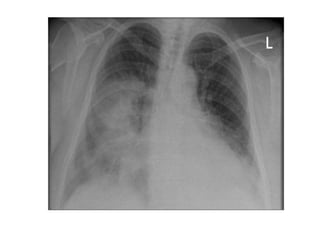

Histoplasmosis: Rx de tórax

• Linfadenopatía en mediastino

(calcificación en formas crónicas)

• Infiltrados en placas

• Con menos frecuencia:

– Cavitación

– Atelectasias por obstrucción debido al

agrandamiento de los ganglios

• En histoplasmosis diseminada patron

micronodular (semeja Tb miliar).

Coccidioidomicosis: Rx de tórax

• Con menos frecuencia (5%):

– Cavitación de paredes delgadas

– Lesiones nodulares numulares

– Derrame pleural

• En coccidioidomicosis diseminada

patron micronodular (semeja Tb miliar).

Blastomicosis: Rx de tórax

• Infiltrados focales alveolares en

lóbulos superiores, a menudo de

aspecto nodular

• Cavitaciones frecuentes (1/3 de los

casos)

• El 15 % masa que se confunde con Ca

• Patron micronodular < del 1%.

• Adenopatías y calcificaciones raras.